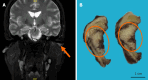

Case summary: A 55-year-old female patient first exhibited signs of illness over 10 years ago with persistent discomfort in the left external auditory canal, accompanied by skin irritation and bleeding. One month prior to seeking professional help, she experienced hearing loss and a sensation of obstruction in the affected ear, intermittently accompanied by ringing sounds, but no dizziness. An unusual mass was detected in the left auditory canal, confirmed through biopsy as moderately differentiated epithelial squamous cancer cells. This led to her admission to our hospital, where the final diagnosis confirmed as "NKSCC linked to a positive DEK::AFF2 fusion". The patient underwent surgical excision, followed by three cycles of local radiation therapy. Yet, metastasis to the lumbar vertebrae occurred 19 months post-treatment, followed by neck lymph node swelling detected three months after a physical examination. The patient died nine months later despite surgical removal of the metastatic lesion.